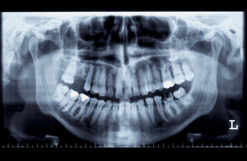

- 치과 의사와의 상담 및 검사: 치과 의사와의 상담을 통해 환자의 상태와 필요한 수술 범위 등을 확인합니다. 검사를 통해 치아와 관련된 질병이나 문제를 파악할 수 있습니다.

- 수술 계획 및 준비: 검사 결과를 바탕으로 수술 계획을 수립하고, 환자의 건강 상태와 약물 복용 여부 등을 확인합니다. 수술 전에는 국소마취나 전신마취 등의 마취 방법을 결정하고, 필요한 경우 항생제 등의 약물을 처방합니다.

- 임플란트 삽입: 치과 의사는 임플란트를 안정적으로 삽입하기 위해 잇몸을 절개하고, 임플란트를 치아 뼈에 삽입합니다. 수술 후에는 굳게 고여있는 결손을 채우기 위해 뼈 이식이 필요한 경우도 있습니다.